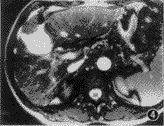

8例(10.8%)病人屏气不佳,TSE T2WI有较严重的呼吸运动伪影。所有病人的true-FISP T2WI有轻微的条纹状伪影,但不影响病变的显示,13例(17.6%)在近膈面或胆囊窝处出现磁化敏感伪影,其中3例掩盖了病灶。epi T2WI与EPI-ld T2WI均有明显的化学位移伪影,在肥胖的病例尤为明显,移位的背部皮下脂肪影重叠于肝脏上,可掩盖肝内病灶(图1),而IR-EPI-ld T2WI上脂肪信号得到很好的抑制,可显示被掩盖的病变(图2)。在膈顶区,所有的EPI序列均出现肝脏的变形,但大多程度较轻,不影响病变的显示。本组所有病人的true-FISP、 HASTE及3个EPI序列T2WI均无明显的呼吸运动伪影。未见因为EPI图像有严重的N/2伪影(鬼影)而不能用于诊断。EPI序列对肝内外解剖结构的显示不及true-FISP及TSE。

各个序列的病变检出率详见表2。对于囊性病变(肝囊肿与海绵状血管瘤),除epi外其他各序列间的检出率无明显差异(χ2=4.739,P>0.05)。各序列均检出所有大于5 cm的实性病变,但EPI序列的病灶与肝实质对比高于true-FISP、HASTE及TSE。直径2~5 cm的实性病变,IR-EPI-ld序列的检出率高于true-FISP(χ2=6.081,P<0.05)和TSE(χ2=3.888,P<0.05),略高于HASTE但无统计学差异(χ2=2.867,P>0.05)。对于直径小于2 cm的实性病灶,IR-EPI-ld序列的检出率明显高于true-FISP(χ2=23.76,P<0.001)、HASTE(χ2=11.85,P<0.001)及TSE(χ2=14.26,P<0.001)(图1~7)。1例肝硬化增生结节癌变,IR-EPI-ld T2WI清楚显示了结节内的癌变灶(图8~10)。在带有低度扩散梯度场的IR-EPI-ld与EPI-ld T2WI图像中,血管断面呈明显低信号,容易与小病灶区分(图11,12)。

图1~3 女,56岁,胰腺囊腺癌,肝脏多发转移。图1为EPI-ld T2WI,肝左内叶肿块呈明显高信号,肝右叶见2个高信号结节灶(箭头),其中偏后方的结节灶被化学位移伪影掩盖;图2为IR-EPI-ld T2WI,化学位移伪影明显减轻,病灶充分暴露(箭头);图3为true-FISP T2WI,左内叶见一略高信号肿块(○),右肝未见病灶